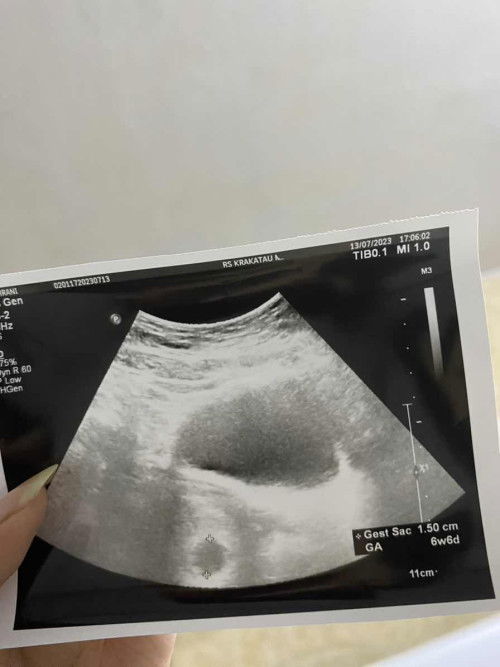

kantung kehamilan tidak bulat

bun, mau nanya adakah yg kantung kehamilannya ga bulat seperti ini. berdasarkan hpht harusnya 8w, usg 6w2d. dan suka kram perut seperi mau haid tp ringan